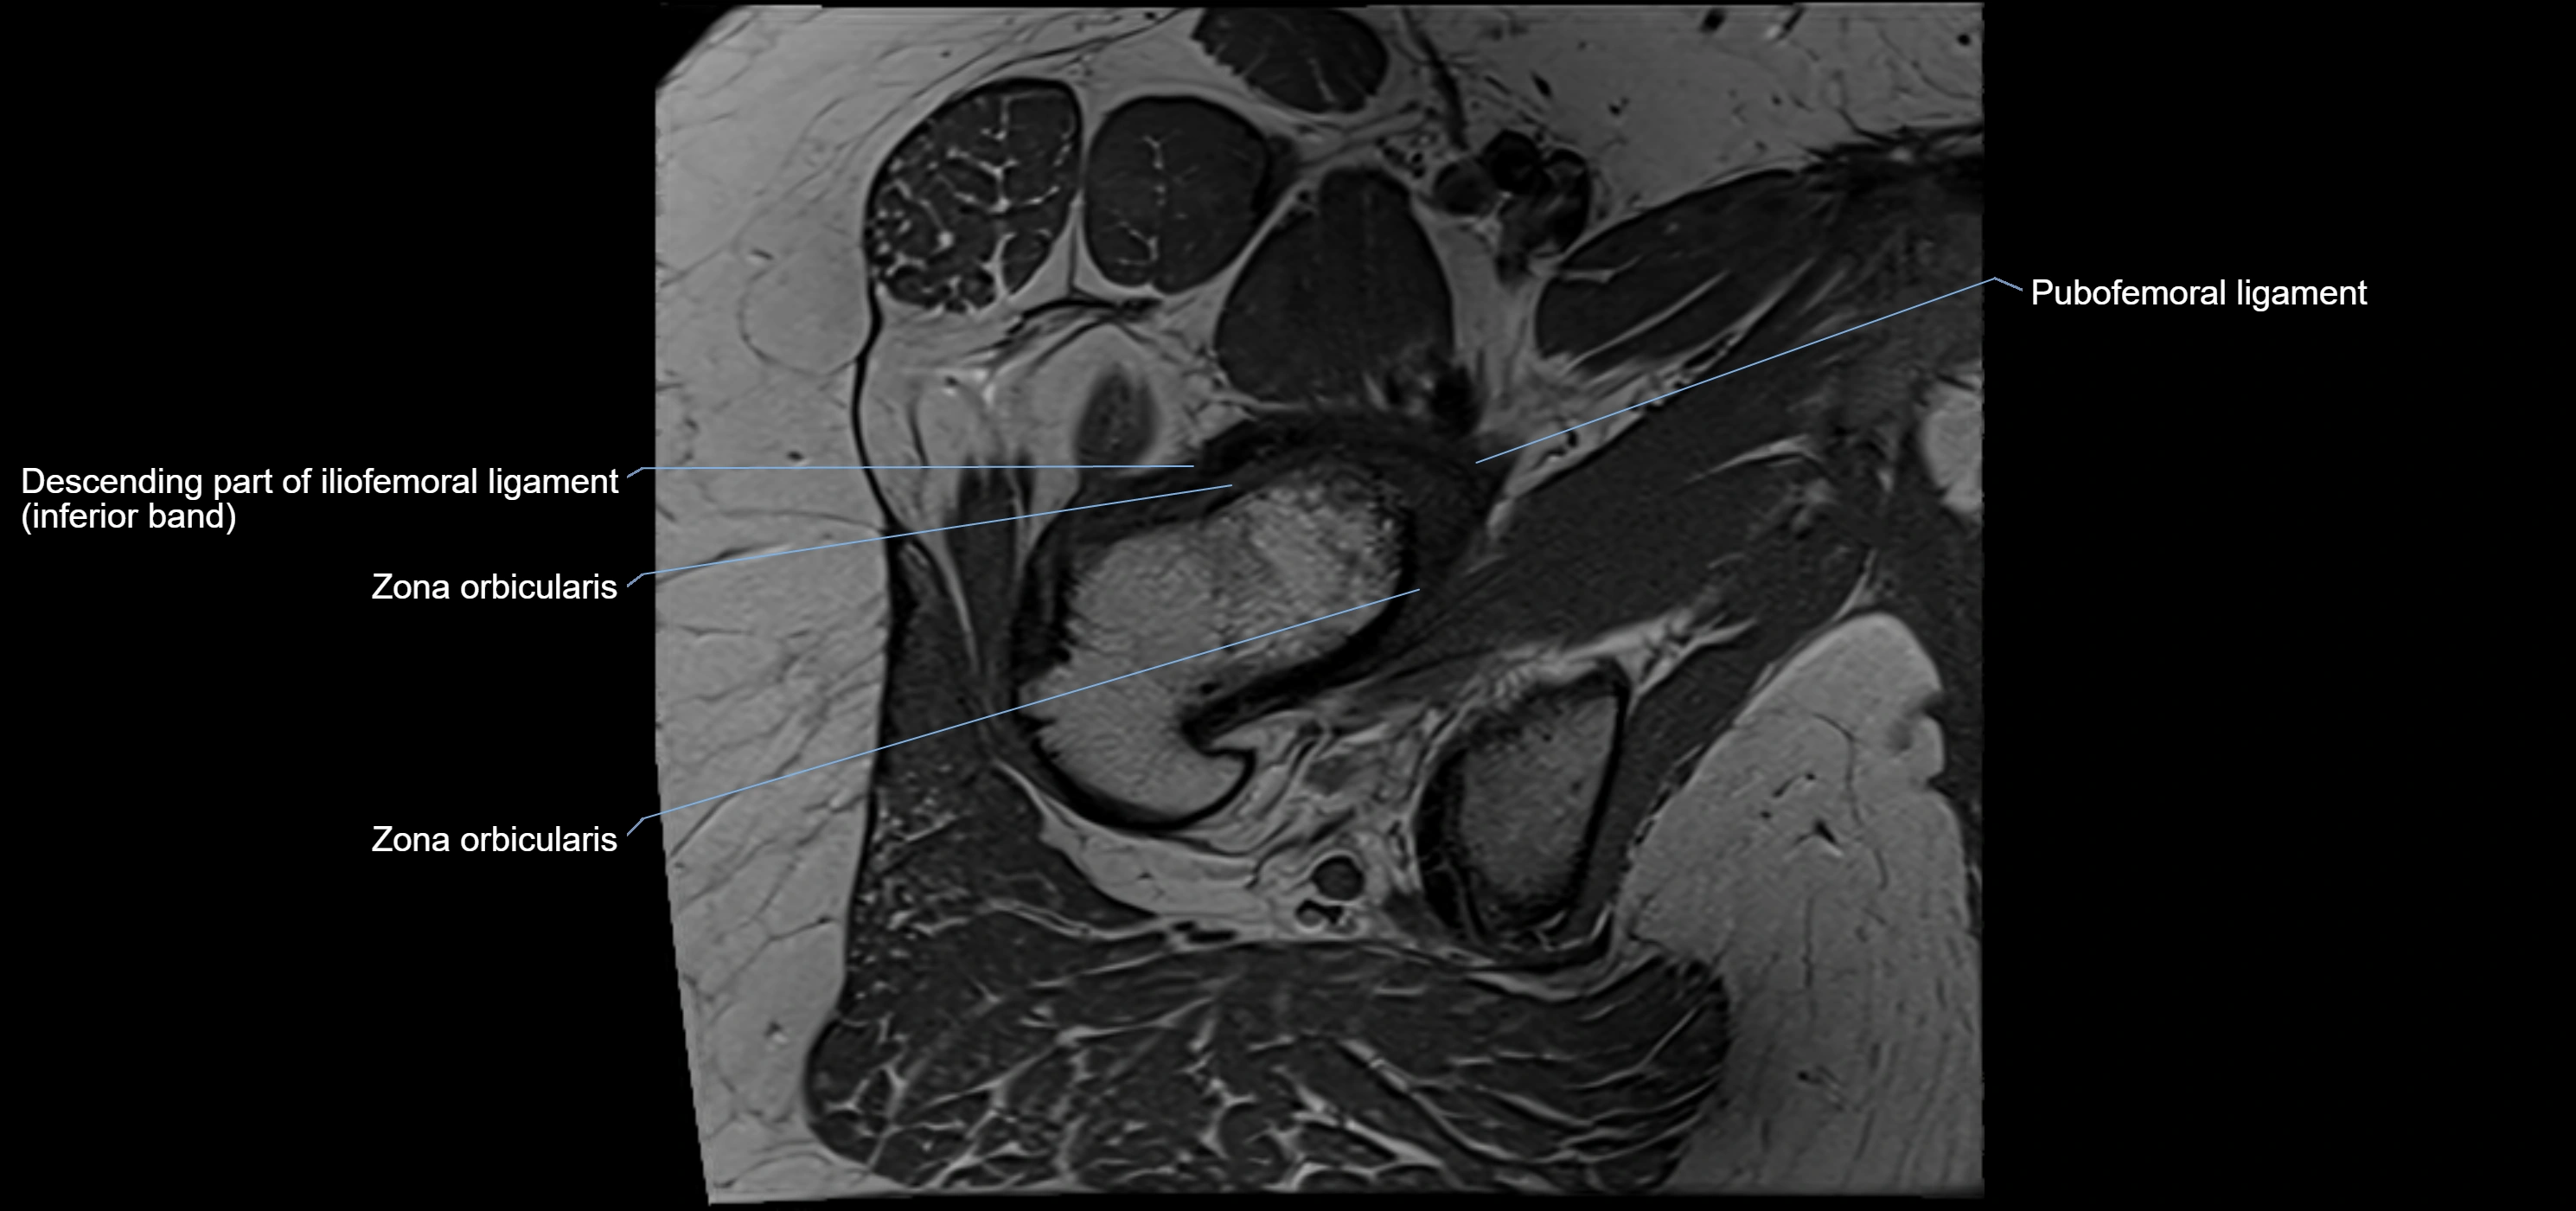

MRI image

image

MRI Appearance

T1-weighted images:

• Labrum: low signal intensity (dark)

• Surrounded by intermediate signal joint fluid (bright on arthrogram)

• Tears: linear or focal areas of intermediate-to-high signal interrupting labral continuity

T2-weighted images:

• Joint fluid: bright, making labral tears visible as fluid extending into or around labrum

• Degeneration: may show areas of increased signal within labrum